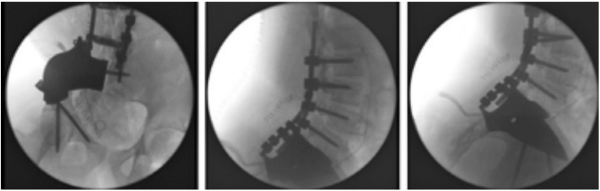

הטיפול הקרינתי משמש חלופה או תוספת לטיפול הניתוחי. גם בסרקומה על שם יואינג וגם באוסטאוסרקומה, יש אפשרות לטיפול קרינתי כאשר לא ניתן לכרות את הגידול בצורה יעילה ומשמעותית מבחינה אונקולוגית. מצב כזה מתרחש לעיתים באתרים אופייניים, בעיקר בראש-צוואר ובעמוד השדרה. במצבים כאלו נבחר להשתמש במינוני קרינה מוגברים כדי להבטיח טיפול מספק בגידול הממאיר.

המהפכה המשמעותית בטיפול קרינתי בגידולים ממאירים היא במעבר מקרינה בחלקיק הפוטון (photon particle) לחלקיק הפרוטון (proton particle). שינוי זה, שהיריעה כאן קצרה מלדון בו לעומק, הוביל ליכולת הקרנה טובה ויעילה, כמו בשיטות קודמות, תוך הקטנה משמעותית של הקרינה הסביבתית, אשר גורמת נזק ופוגעת באיברים שכנים. ישנם מחקרים אשר מוכיחים שחלופה זו יעילה ובטוחה, ולתחושתנו, בשנים הקרובות הרוב המכריע של החולים יקבל קרינה בצורה זו.